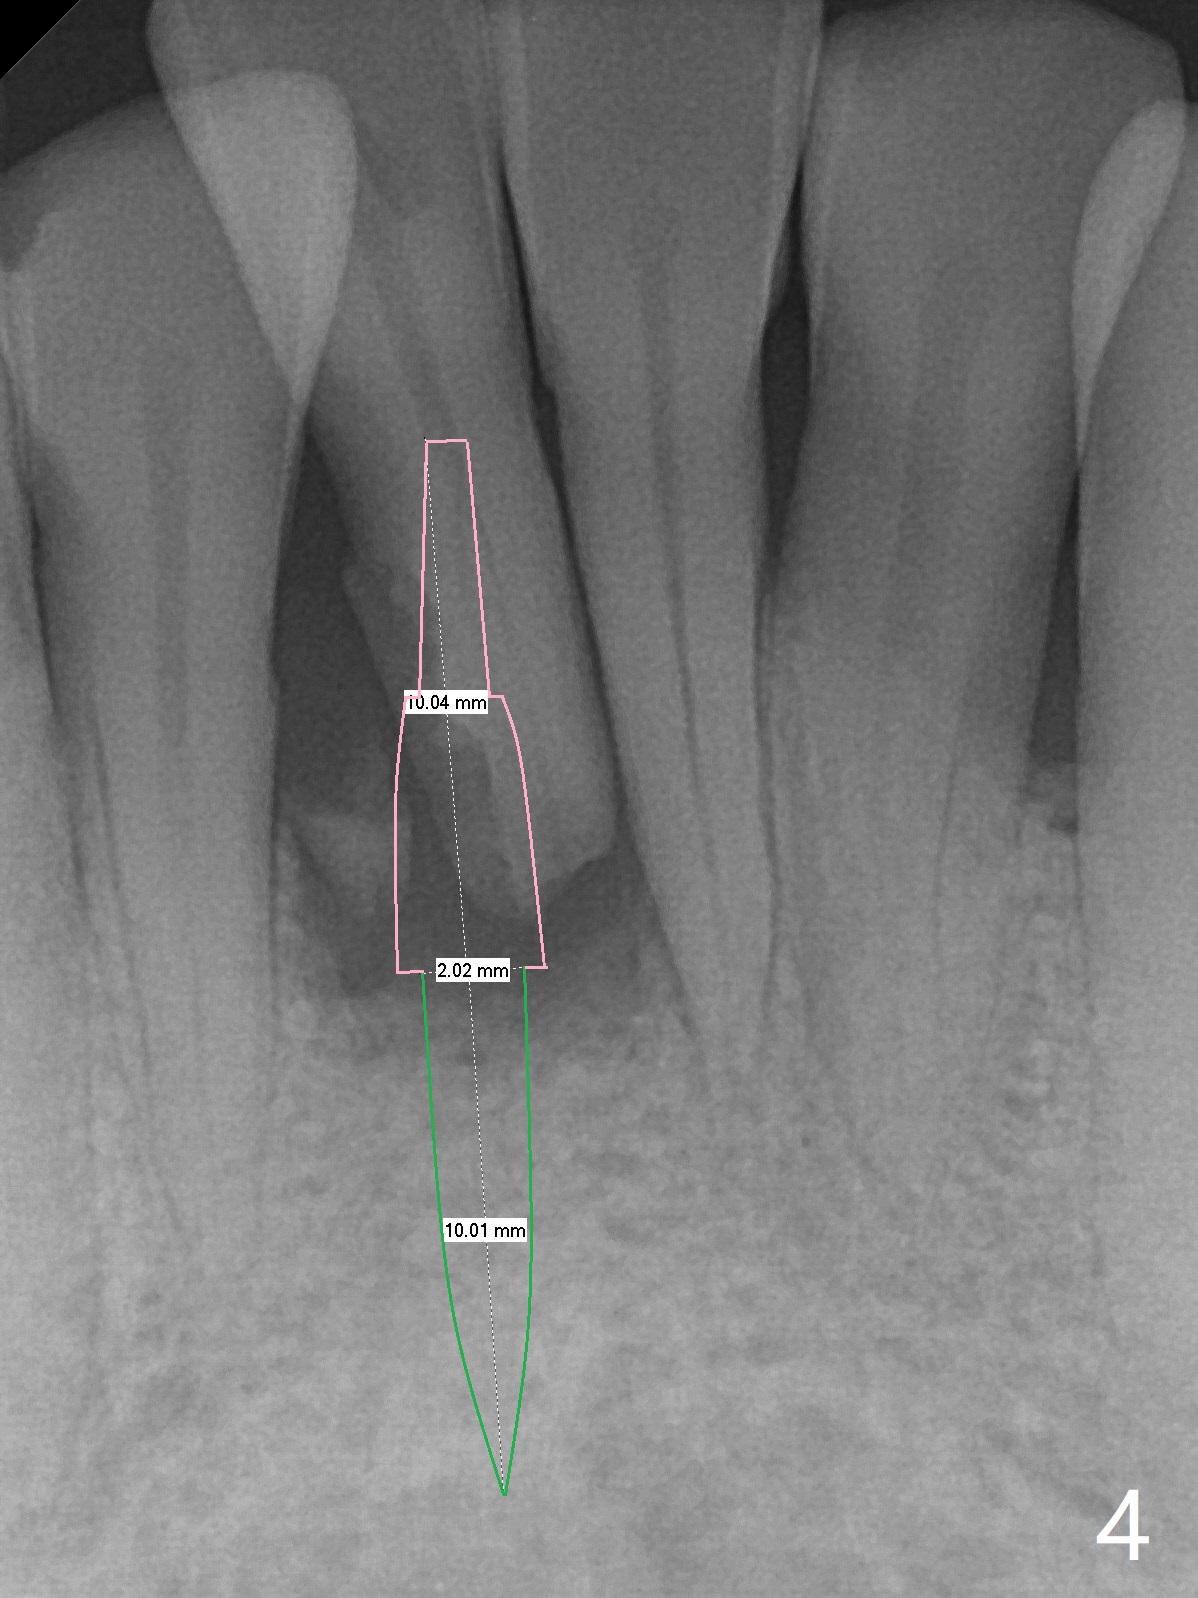

A 47-year-old man, a possible bruxer (Fig.1), is concerned about the mobile 2nd molar and lower central incisor (Fig.2,3). To prevent periimplantitis, a 2 mm 1-piece implant and a short one (5x5 mm) will be placed subcrestal at these sites, respectively (Fig.4,5). Sticky bone is a must. Pulpal test will determine whether RCT is required for #30 (Fig.5 curved white line). In fact the tooth #30 is tested to be vital. Onlay graft is an option for #31 (Fig.6 red rectangle). There is history of #32 extraction. The severely periodontally affected tooth #25 (Fig.7 *) has narrow mesiodistal space (Fig.8). It is the best treated with extraction with bone graft and self drifting.